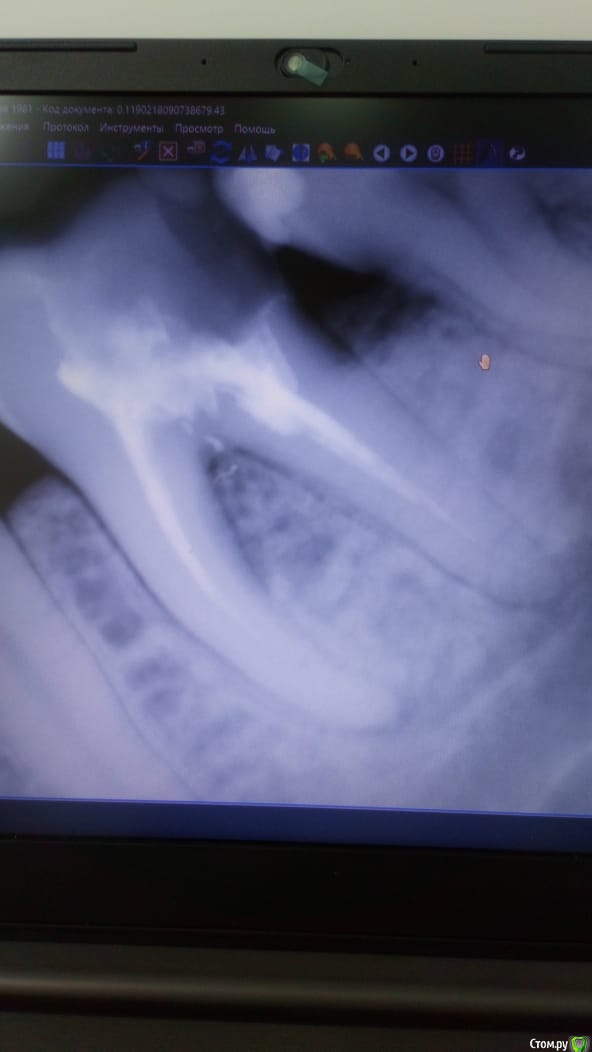

Dassety Опубликовано 10 марта, 2020 Автор Поделиться Опубликовано 10 марта, 2020 Зуб, 5-ка (большой жевательный слева снизу). Снимки прилагаю до склеивания и после. Ссылка на комментарий

Dassety Опубликовано 10 марта, 2020 Поделиться Опубликовано 10 марта, 2020 Добрый день! Обратилась к стоматологу по причине вылетевшей пломбы. Зуб сам по себе не беспокоил. Врач сказала, что нужно чистить каналы и пломбировать их. Сделали эту процедуру. Зуб несколько дней поболел, потом перестал. Спустя месяц почувствовала, что мне больно на негл верхней челюстью нажимать. Обратилась снова к врачу, сняли пломбу. Продезинфицировали. Одели временную пломбу. С временной пломбой было чуть легче, но все равно ощущался дискомфорт. Пришла на прием, обьяснила, что улучшения нет. Врач поставила мне постоянную пломбу и сказала, что у мпня воспалена десна, вся проблема в этом. Лечите, мол, десну Метрогил-дента. Через день зуб еще сильнее начал беспокоить при накусывании. Пришла к врачу. Она решила, что плохо прошла каналы или пропустила один из них. Решили перелечить повторно. И тут она инструментом куда то попала, что мне стало очень больно. Она сделала снимок с инструментом. Оказалось, что это перфорация между корней зуба. На снимке воспаление с этой области. Хотя на первоначальном снимке ни воспаления, ни перфорации не видно было. Врач склеила мне трещину Триметродексом. Сказала, что теперь нужно время, чтобы восстановилась косная ткань. Вот уже неделя прошла, а мне так же больно накусывать на зуб и надавливать на него с боков и сверху тоже больно. Скажите, пожалуйста, в чем была ошибка врача и правильно ли сейчас она все сделала? Есть ли шанс спасти зуб? Заранее спасибо всем откликнувшимся. Ссылка на комментарий